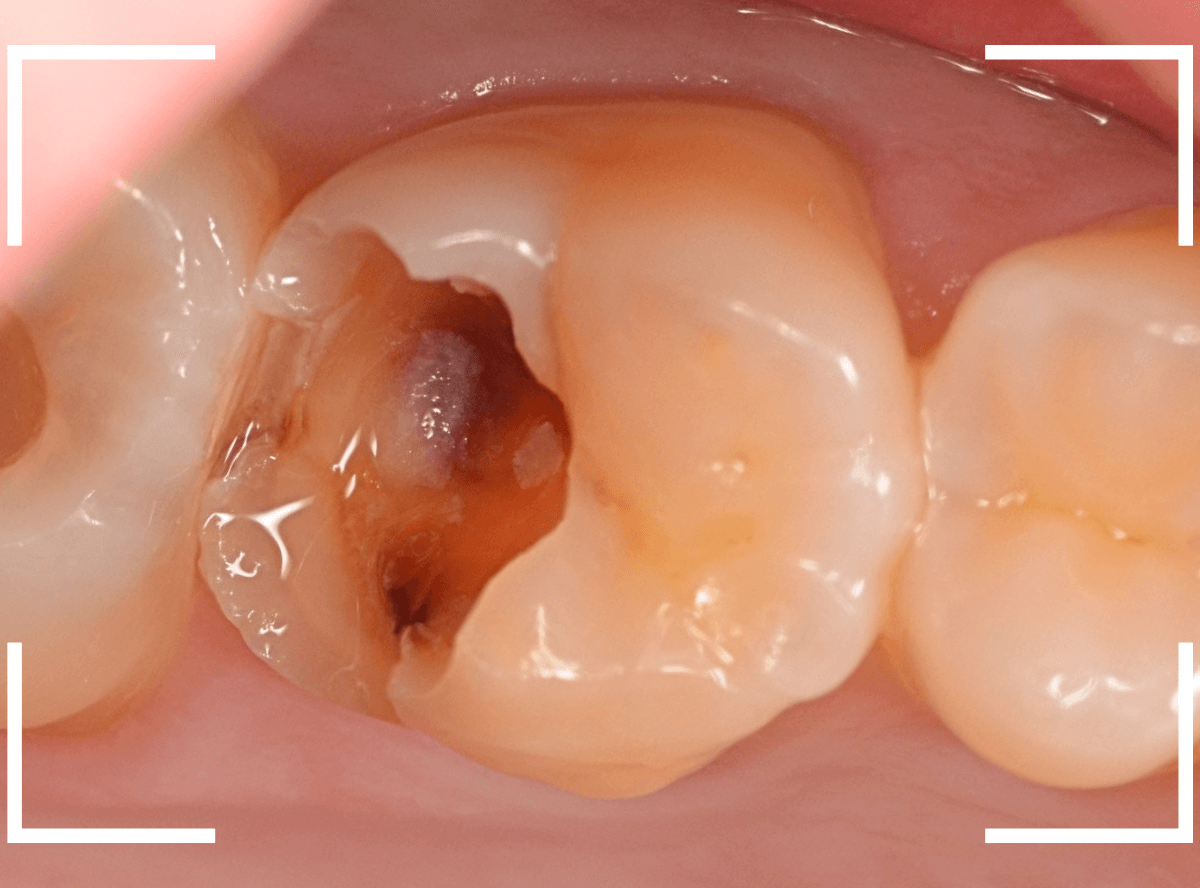

Case.15 レジンの下の深い虫歯

奥歯で咬んだ時に、痛みを感じるという訴えで来院された患者さんです。

パッと見は特に問題なさそうな状態ですが、大きなレジン治療がしてあり、レジンの奥もボヤっと黒っぽく見えてアヤシイ感じです。

麻酔をして、レジンを外します。

レントゲン写真から想定できるような大きな虫歯ですね。

慎重に虫歯を除去します。

赤く染色されている部分が虫歯の残っている部分です。

全ての虫歯を除去したところです。

何とか神経の寸前で虫歯を食い止める事ができましたが、まれに症状が出る事もありますのでお薬をつめてしばらく経過観察します。